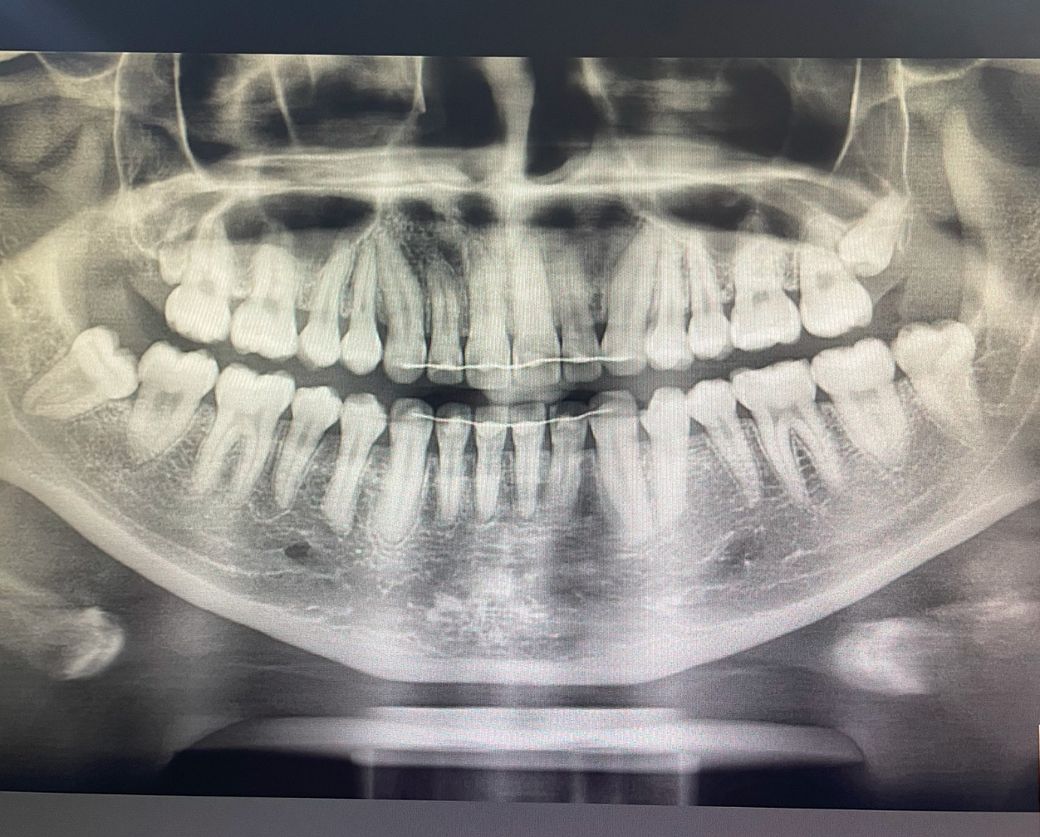

안녕하세요 위의 오른쪽 사랑니가 매복인데사랑니 자라는 방향이 너무 어금니 뿌리랑 맞닿아 있는거 같아서요.. 나중에 뿌리를 녹일까 걱정이 돼서 그런데 뽑는게 맞을까요??

사랑니로 인하여 어금니의 충치나 뿌리 흡수 등의 가능성이 없진 않아보이며 빼는 게 좋습니다.

위쪽 사랑니는 크게 문제가 되진 않을것같지만 사진상 오른쪽 아래 사랑니는 관리가 안되면 앞치아 충치가 생길 가능성이 높은거 같습니다 .

의사마다 사랑니 발치의 시기나 필요성에 대해 생각하는 바가 다른데요. 개인적으로는 저렇게

앞 치아에 걸려있으면 충치나 염증을 야기하는

경우가 많고 나이가 들수록 뼈의 탄성이 줄어들어 점점 발치하기가 힘들어져 예방적으로 발치를 추천드리는 편입니다. 다만 환자분 같은 경우에는 뿌리끝이 신경관과 근접해있어 ct촬영후에 재평가할 것 같습니다.

그래서 사진으로만 봤을 경우에는 이미 다 완성되어 있는 사랑니로 보입니다. 해당 치아가 앞에 있는 치아에 뿌리를 흡수할 가능성은 매우 낮아 보입니다. 기울어진 치아가 잇몸에 부분적으로 노출이 되면 이물질이 끼게되고 문제를 발생시킬 수 있어.

예방 차원에서 발치를 하는 것이 좋을 수 있습니다. 자세한 확인을 위해서 치과에서 진료를 받아보는 것을 권유드립니다.

사진상 오른쪽 위, 왼쪽 아래는 사랑니가 매복이면서 옆 어금니에 기대고 있기 때문에 옆 어금니의 치근 흡수, 충치유발 가능성이 좀 있긴 합니다

다만 상악 수평매복 사랑니의 경우 발치 난이도가 높고 뼈도 많이 삭제해야해서 그냥 두는 경우도 많습니다